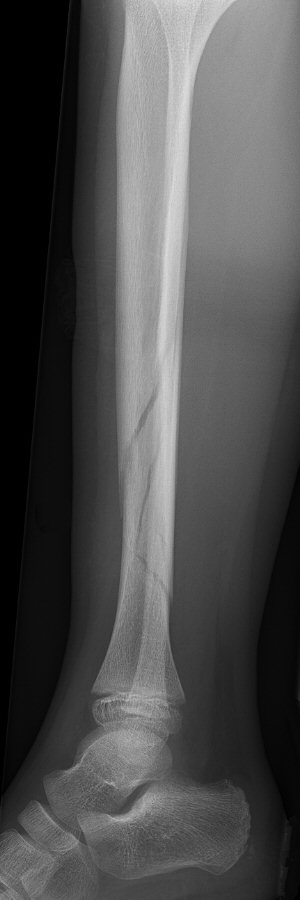

Tibiafraktur hos 7-åring, behandlades med gipsstövel

|